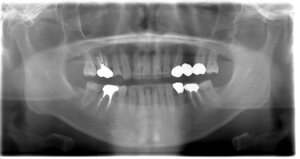

インプラントの症例1

レントゲン写真①

レントゲン写真②

レントゲン写真③

年齢・性別 30代・男性

主訴 左下7番のインプラント

治療内容 右下7番は歯根破折により抜歯した。その後欠損補綴をインプラントにて行った。

抜歯時間 13ヶ月

抜歯費用 合計:627,000円